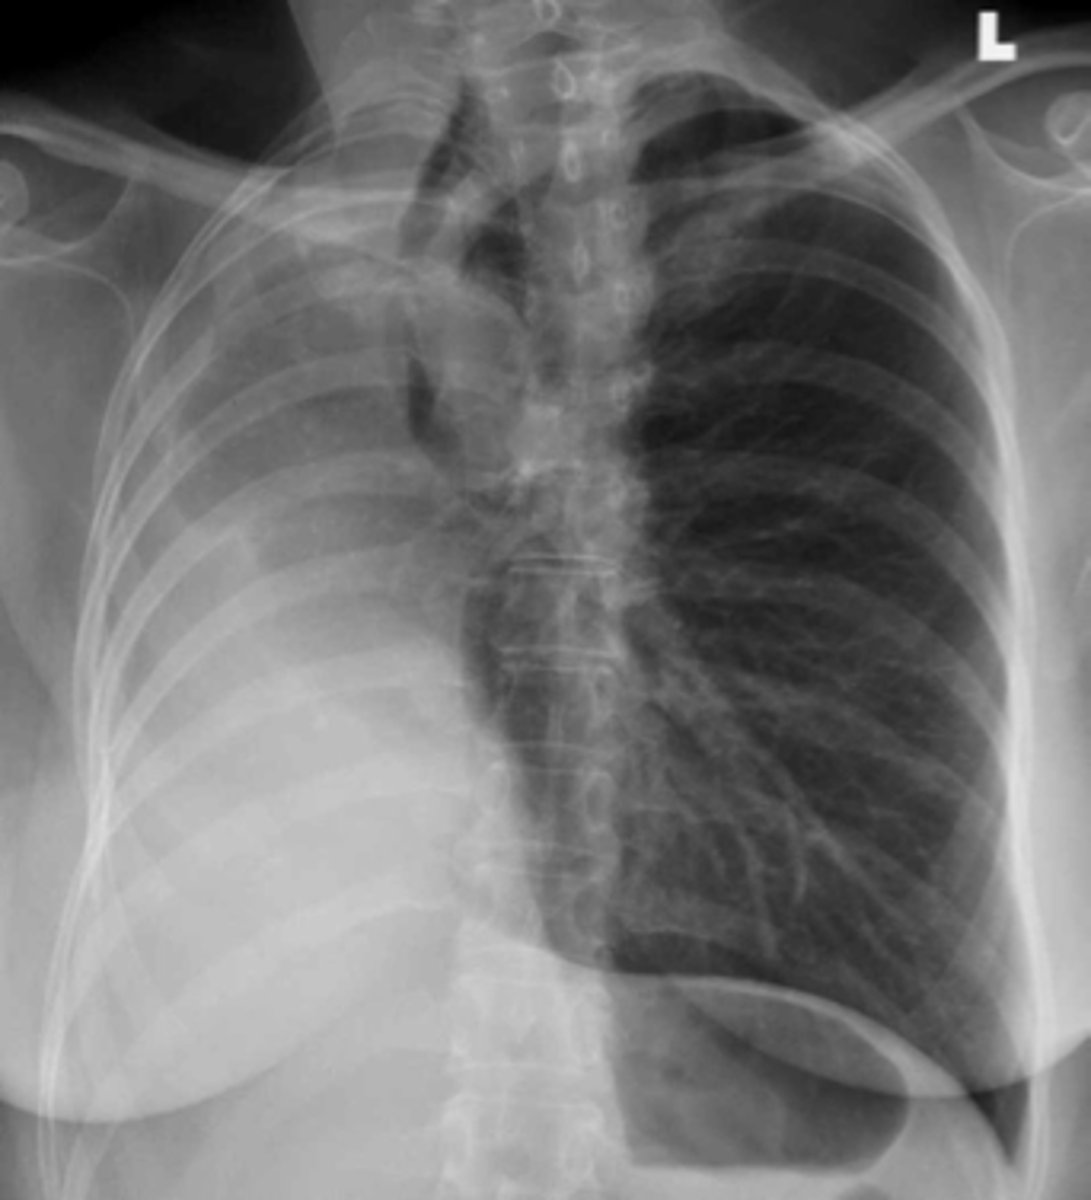

Tension pneumothorax

knowt flashcard image

Tension pneumothorax (right)